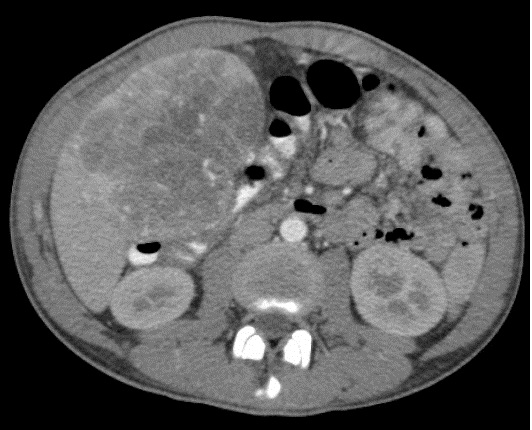

Image TDM du carcinome

hepatocellulaire du foie : Image du masse a hypodense

du foie avec rehaussement au temps arteriel et " wash out "

au temps portal .

Aspect d'une masse a

hypodense du carcinoma hepatocellulaire du foie

droit ( fleche rouge ) . Image radiologique TDM en

coupe axiale en phase non injecte |